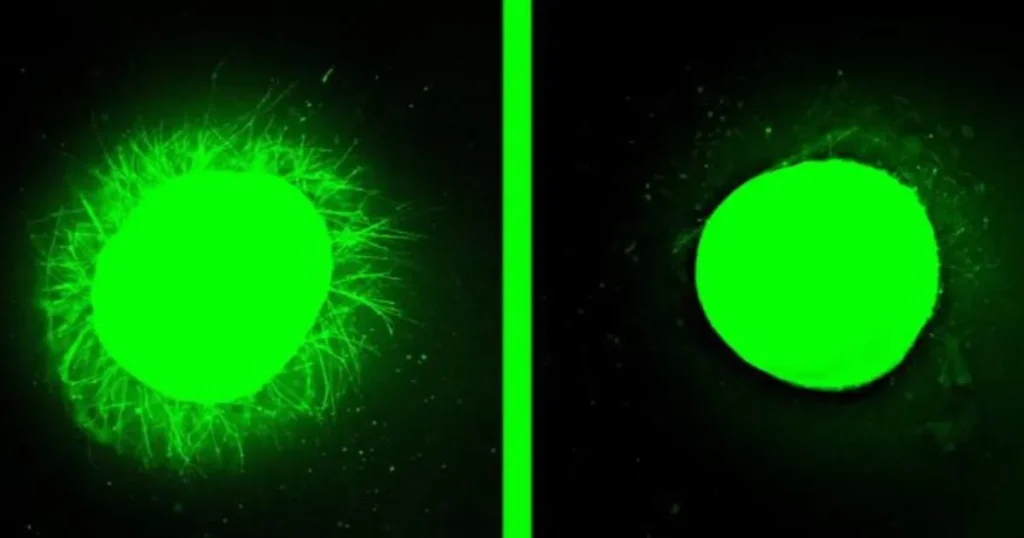

أظهرت النتائج المجهرية زيادة واضحة في نمو الامتدادات العصبية في العضيات المصابة التي عولجت بالعلاج التجريبي، مقارنة بالعينات غير المعالجة. كانت الامتدادات العصبية في العينات المعالجة بالجزيئات الأكثر حركة أطول وأكثر كثافة، مما يعكس فعالية أعلى في تحفيز النمو العصبي.

شهدت العضيات المصابة التي خضعت للعلاج تراجعًا ملحوظًا في الأنسجة الشبيهة بالندبة الدبقية، حتى أصبحت بالكاد قابلة للكشف. ويأتي هذا التقدم بأمل متجدد لتحسين نتائج المرضى المصابين بإصابات الحبل الشوكي، خاصة وأن العلاج حصل مؤخرًا على تصنيف “دواء يتيم” من إدارة الغذاء والدواء الأميركية (FDA).

وأوضح الباحث الرئيسي في الدراسة، صامويل ستوب، أن هذه العضيات تتيح اختبار العلاجات في نسيج بشري حقيقي بطريقة لا يمكن تحقيقها إلا من خلال التجربة السريرية. وقد تطابق نمو الامتدادات العصبية وتلاشي الندبة الدبقية التي لوحظت في العضيات مع النتائج السابقة في النماذج الحيوانية، مما يعزز احتمال نجاح العلاج لدى البشر.